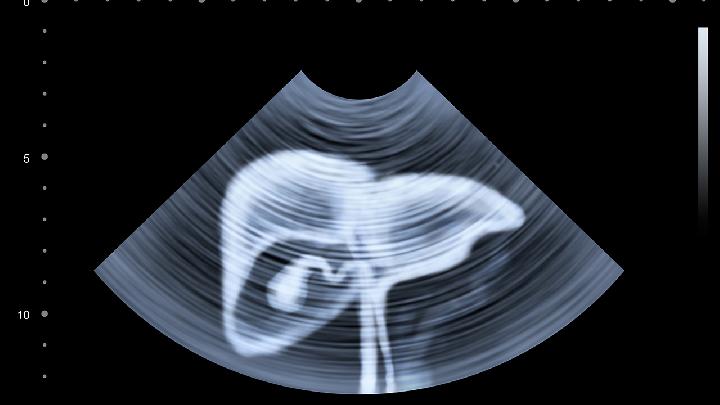

目前,要确定身体内是否患有胆结石病已经是一件很容易的事,只要去医院作个B超检发现胆囊或胆管内有强光团伴声影,是典型的胆结石表现,诊断准确性高达98%。注意 B胆结石应空腹超检,早上不吃任何东西,其目的是提高诊断的准确性。